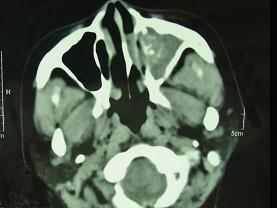

男,41岁,左侧鼻腔胀痛半年余,CT检查如图,最可能诊断为 ( )

• A.真菌性鼻窦炎

• B.出血坏死性息肉

• C.变应性鼻窦炎

• D.化脓性鼻窦炎

• E.上颌窦癌

答案: A